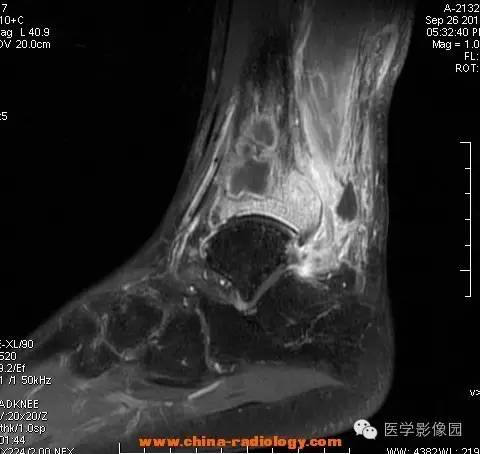

影像学表现:胫骨中下段干骺端不未规则形长T1长T2信号,T2WI见不完整环形稍低信号影,T2脂肪抑制低信号更明显,并见胫骨下段及踝关节后外侧软组织呈弥漫稍高信号,增强明显不均匀强化,增强见低信号环内有环形强化影。

影像学表现:表现为长骨干骺端有椭圆形密度减低区,边缘有清晰的骨质硬化,病变与邻近正常骨髓腔境界清楚。MRI上T1WI呈低信号,少数呈等信号,T2WI多为混杂高信号,增强扫描可见环状强化,强化的脓肿壁薄而均匀。